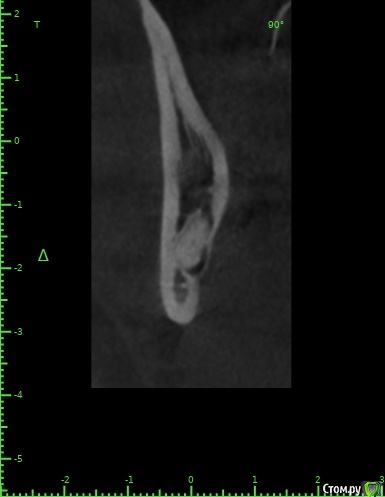

zumanok Опубликовано 15 февраля, 2021 Поделиться Опубликовано 15 февраля, 2021 Коллеги достаточно часто встречаюсь с такой картинкой на КТ в области ментального отверстия . Считаете ли вы это частью тройничного нерва или не обращать внимания? Ссылка на комментарий

Doctor Vlad Опубликовано 15 февраля, 2021 Поделиться Опубликовано 15 февраля, 2021 Коллеги достаточно часто встречаюсь с такой картинкой на КТ в области ментального отверстия . Считаете ли вы это частью тройничного нерва или не обращать внимания там что угодно может быть, больше похоже на пору кости. в этом случае до канала далеко. вы же не собираетесь так глубить? Ссылка на комментарий

zumanok Опубликовано 15 февраля, 2021 Поделиться Опубликовано 15 февраля, 2021 (изменено) там что угодно может быть, больше похоже на пору кости. в этом случае до канала далеко. вы же не собираетесь так глубить?Интересно может быть такая форма канала или стоит взять винт подлиньше? Примерно так и собирался, мб на пол мм выше. Объясните пожалуйста почему не стоит? Кроме того что коронка на 1 мм подлиньше будет. Изменено 15 февраля, 2021 пользователем zumanok Ссылка на комментарий

Doctor Vlad Опубликовано 16 февраля, 2021 Поделиться Опубликовано 16 февраля, 2021 Интересно может быть такая форма канала или стоит взять винт подлиньше? Примерно так и собирался, мб на пол мм выше. Объясните пожалуйста почему не стоит? Кроме того что коронка на 1 мм подлиньше будет.скорей всего там нерва нет и это не канал. Но. А если есть)? Ссылка на комментарий

zumanok Опубликовано 16 февраля, 2021 Поделиться Опубликовано 16 февраля, 2021 (изменено) скорей всего там нерва нет и это не канал. Но. А если есть)?Да вот,для этого и выбрал 3.5 на 8.5. Сам склоняюсь к тому что костный рисунок, информации о таком строении нерва не нашел. Думаю в процессе препарирования ложа посмотреть, если будет чувствительность то не лезть дальше.Подскажите чем Вас смутила глубина установки имплантата? Только этим образованием?По КТ 1.5мм до него. Изменено 16 февраля, 2021 пользователем zumanok Ссылка на комментарий

Raystom Опубликовано 16 февраля, 2021 Поделиться Опубликовано 16 февраля, 2021 Там будет не чувствительность, а резкий провал фрезы после определенного момента препарирования, если не отслеживать момент с глубиной, чем напугаете и себя и пациента. По поводу рисунка может быть как и костный рисунок, так и петля нижнелуночкого канала, зачем проверять? Ссылка на комментарий

Doctor Vlad Опубликовано 16 февраля, 2021 Поделиться Опубликовано 16 февраля, 2021 Да вот,для этого и выбрал 3.5 на 8.5. Сам склоняюсь к тому что костный рисунок, информации о таком строении нерва не нашел. Думаю в процессе препарирования ложа посмотреть, если будет чувствительность то не лезть дальше.Подскажите чем Вас смутила глубина установки имплантата? Только этим образованием?По КТ 1.5мм до него.как он нарисован норм, длиннее не стал бы, чтобы запас был. Просто, по вашим фото не совсем видно где канал. иногда и по кт все очень смутно. особенно когда огромные поры. Ссылка на комментарий